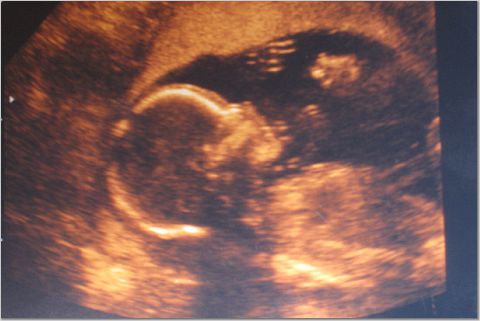

I just wanted to write a quick note and let everyone know that we went for our 20 week (5 month) sonogram this morning.

Most importantly, everything is moving along very nicely. Both twins are growing on schedule, all the organs are in place, and there are no signs of any problems.

I have attached a few sonogram photos. The third picture is our favorite, as you can see both heads in the same shot.